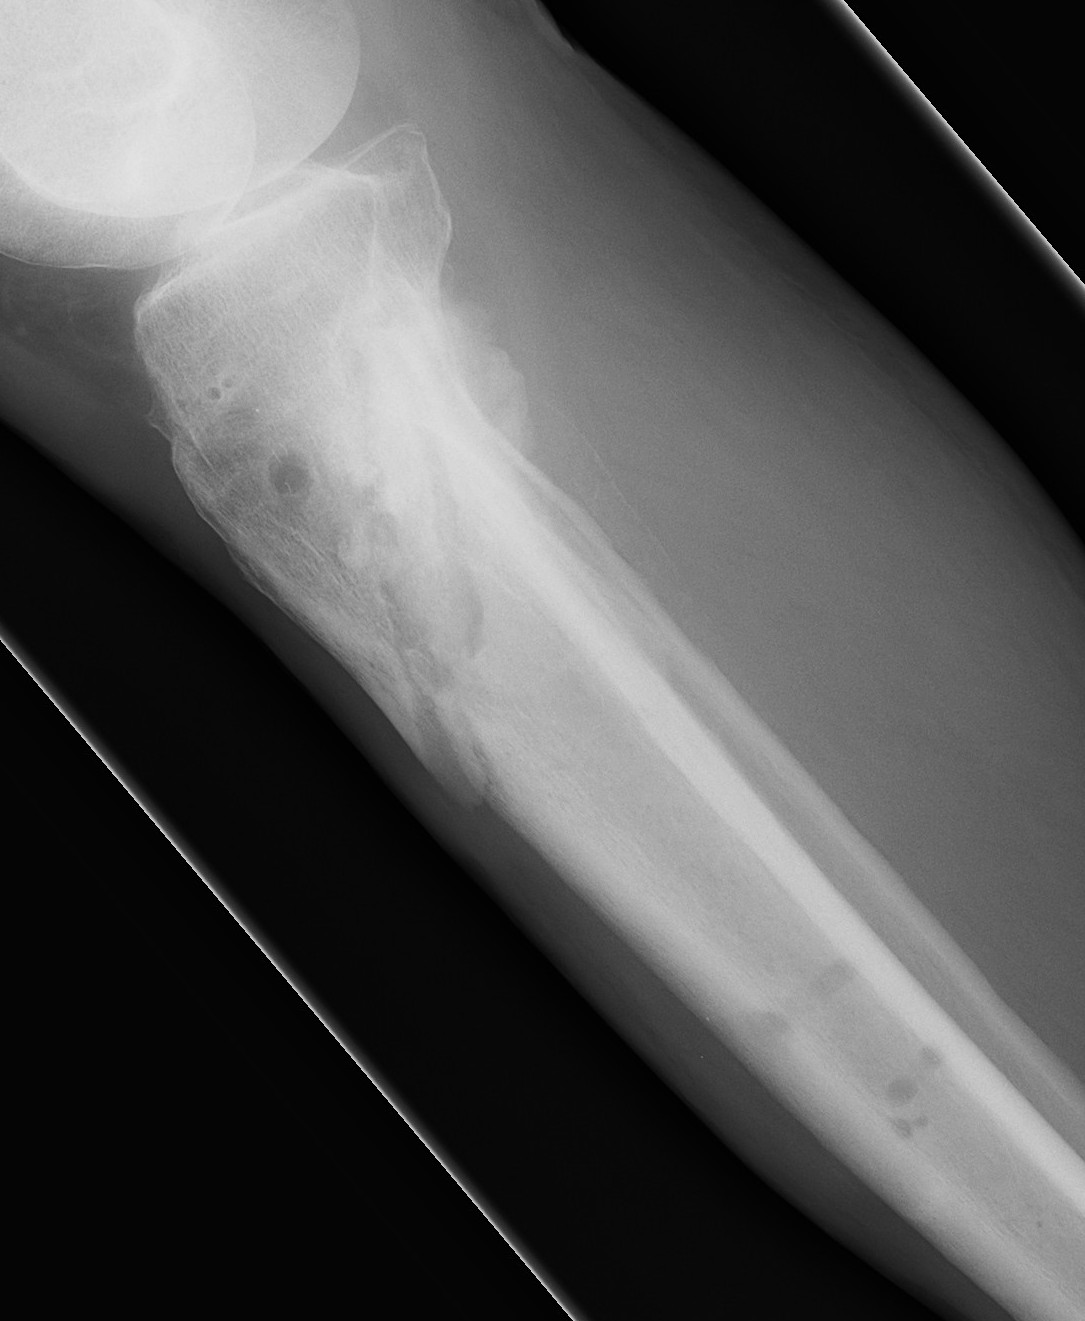

AP View Angulation + Translation

Lateral View Angulation + Translation

Axial Translation (Shortening)

Axial View Angulation

Set Origin / Corresponding Point on AP and Lateral

Origin

- reference fragment

Corresponding point

- on moving fragment